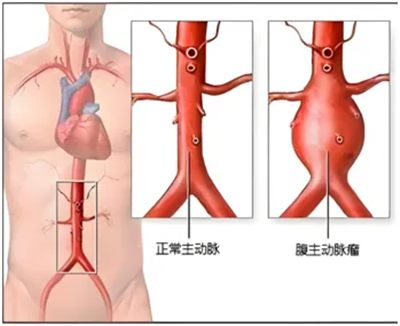

腹主动脉,是人体供应下半身血液的“主干道”。当某一段血管壁因老化、损伤等原因变得脆弱,在血流冲击下像气球一样膨出,就形成了腹主动脉瘤。

▲ 正常腹主动脉与腹主动脉瘤样扩张对比

需要注意的是,它虽然名字带“瘤”,却与恶性肿瘤完全不同。其真正的危险在于,瘤体在血流不断冲击下会逐渐增大、变薄,最终像吹爆的气球一样突然破裂,引发致命性大出血,因此被称为“腹中的不定时炸弹”。